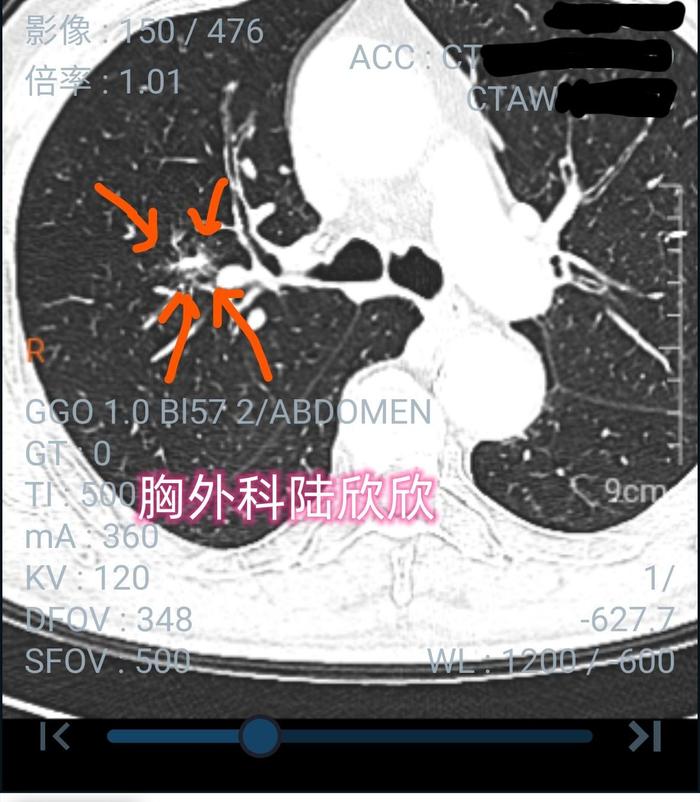

我不存在这个关注点。因为我一般不会漏诊5毫米以上的肺结节。有一次,遇见一个河北病人,已经找江苏省的一个外院名医看过了。名医在自己医院的电脑上看了看,说有一个左上肺的35毫米磨玻璃结节,要住院手术。家属来找我看CT。我在门诊用我的华为手机扫描外院的CT二*维码,看了10分钟后,说:“病人还有两个肺结节,估计江苏省某某医院的医生看不见,你看,这是一个不典型的右上肺结节,大约20毫米,有一个囊腔;还有一个20毫米的不典型混合磨玻璃结节,靠近肺门。因为这两个肺结节不典型,所以一般的医生看不见。双侧肺的三个结节要整体考虑治疗方案。”河北病人家属看了看,说:“确实右上肺有两个结节。昨天,我们找的另外一家医院最有名的医生,在门诊电脑上看他们医院的CT,没想到会看不见两个这么大的结节,更没想到你在手机上这么小的屏幕上能够看见。”家属商量后到我这儿住院。我院CT发现病人除了肺结节以外,还有一个新情况,有一个巨大腹主动脉瘤,有可能破裂大出血,所以只能先治疗动脉瘤再治疗肺结节。家属自己找了外院血管外科的名医,转到外院放置腹主动脉内支架了。放置支架是一个手术,按照规定,手术前必须检查胸部CT,以排除新冠肺炎,结果当然没有新冠肺炎。家属找到我说:“血管支架放置的很好,可惜我有点想不通,这家医院的医生也没有看不见你看到的那两个结节,就是右上肺的20毫米和15毫米两个肺结节,现在我是外行都可以看见了。但是这两家大医院就没有人能看见你发现的右上肺两个结节。”我说:“这两个右上肺的结节不典型,看不见很正常。”从这个病人可以看见,漏诊较大的肺结节会导致重大问题,大的磨玻璃结节看不见会导致手术方案出现重大偏差

下图,被忽略的20毫米的右上肺混合磨玻璃结节。